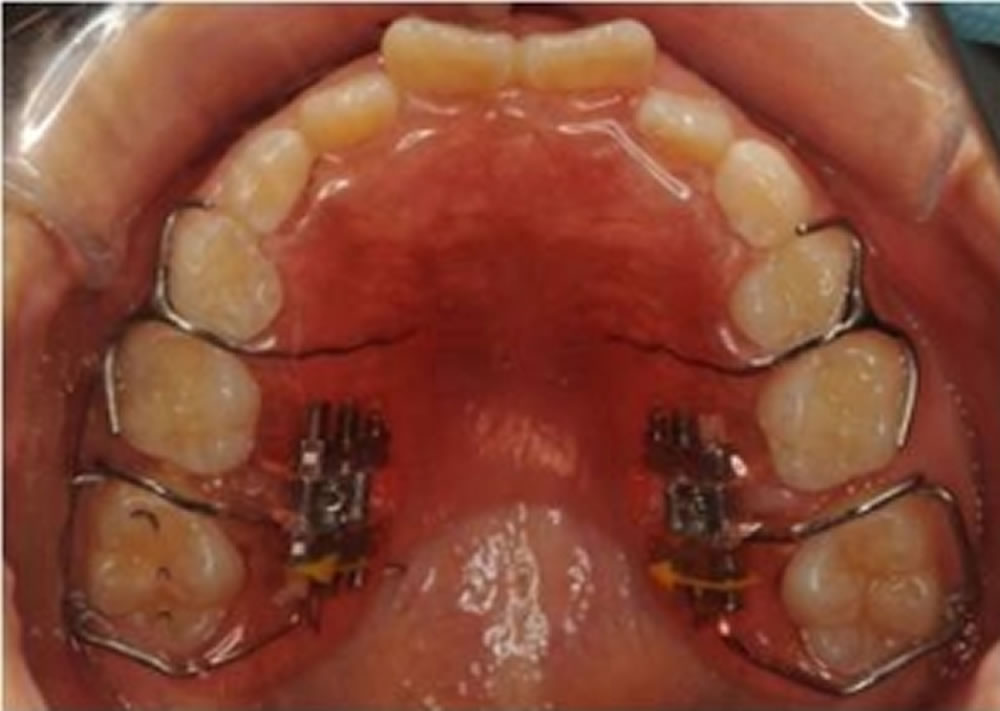

BiVi歯科・矯正歯科で実施した小児矯正の治療例をご紹介

▼当院で実際に行った小児矯正治療の症例をご紹介します。